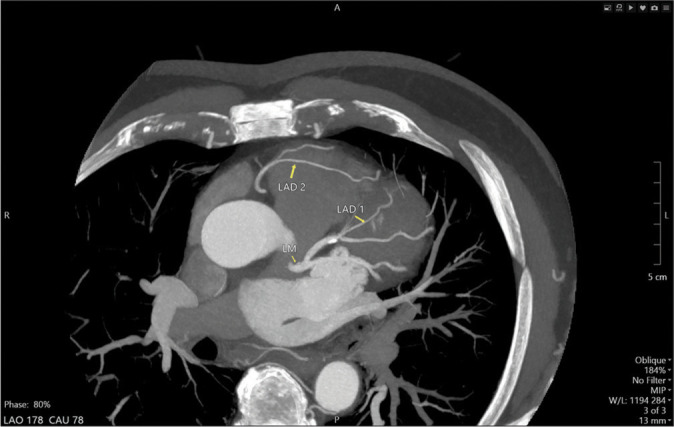

Dual left anterior descending (LAD) coronary artery is a rare anatomical variant with significant clinical implications. Recognizing this variant is crucial for accurate diagnosis and effective management, particularly in the context of revascularization strategies. We present a 71-year-old male with a history of dyspnea on exertion with baseline wall motion abnormality on a transthoracic stress echocardiography irreversible after exercise. Coronary computed tomography angiography revealed a dual LAD system: The left short LAD (LAD1) originating from the left main coronary artery and the right LAD (LAD2) arising separately from the right coronary cusp, distinct from the right coronary artery ostium. Having different origins and courses, both LADs supply the LAD territory. Our case is notable for two main reasons: The rarity of this particular type of dual LAD anatomy and the unique course of the LAD2, which, to our knowledge, has not been described in any previous case report. Although rare, dual LAD coronary artery should be considered in patients with atypical short LAD. Comprehensive imaging and a thorough understanding of coronary artery variants are essential for accurate diagnosis and effective management.

Abstract Image